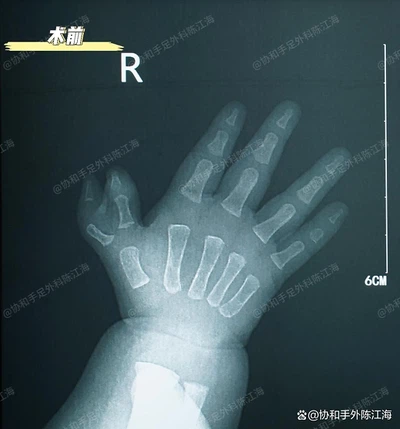

Preoperatwa x - ray

Pou kalite ti bebe sa a nan polydactyly, dirèkteman retire gwo pous siplemantè a ak Lè sa a, fè yon osteotomi realign te pi apwopriye.

Paske gwo pous enteryè a te relativman pi bon nan aparans ak fonksyon, nou deside retire gwo pous la deyò epi ajiste kapsil la jwenti ak lòt estrikti nan gwo pous ki rete a kòmsadwa. Konbine avèk fil postoperatwar k - ak atèl pou determinasyon, apwòch sa a redwi chans pou gwo pous la devye pita.